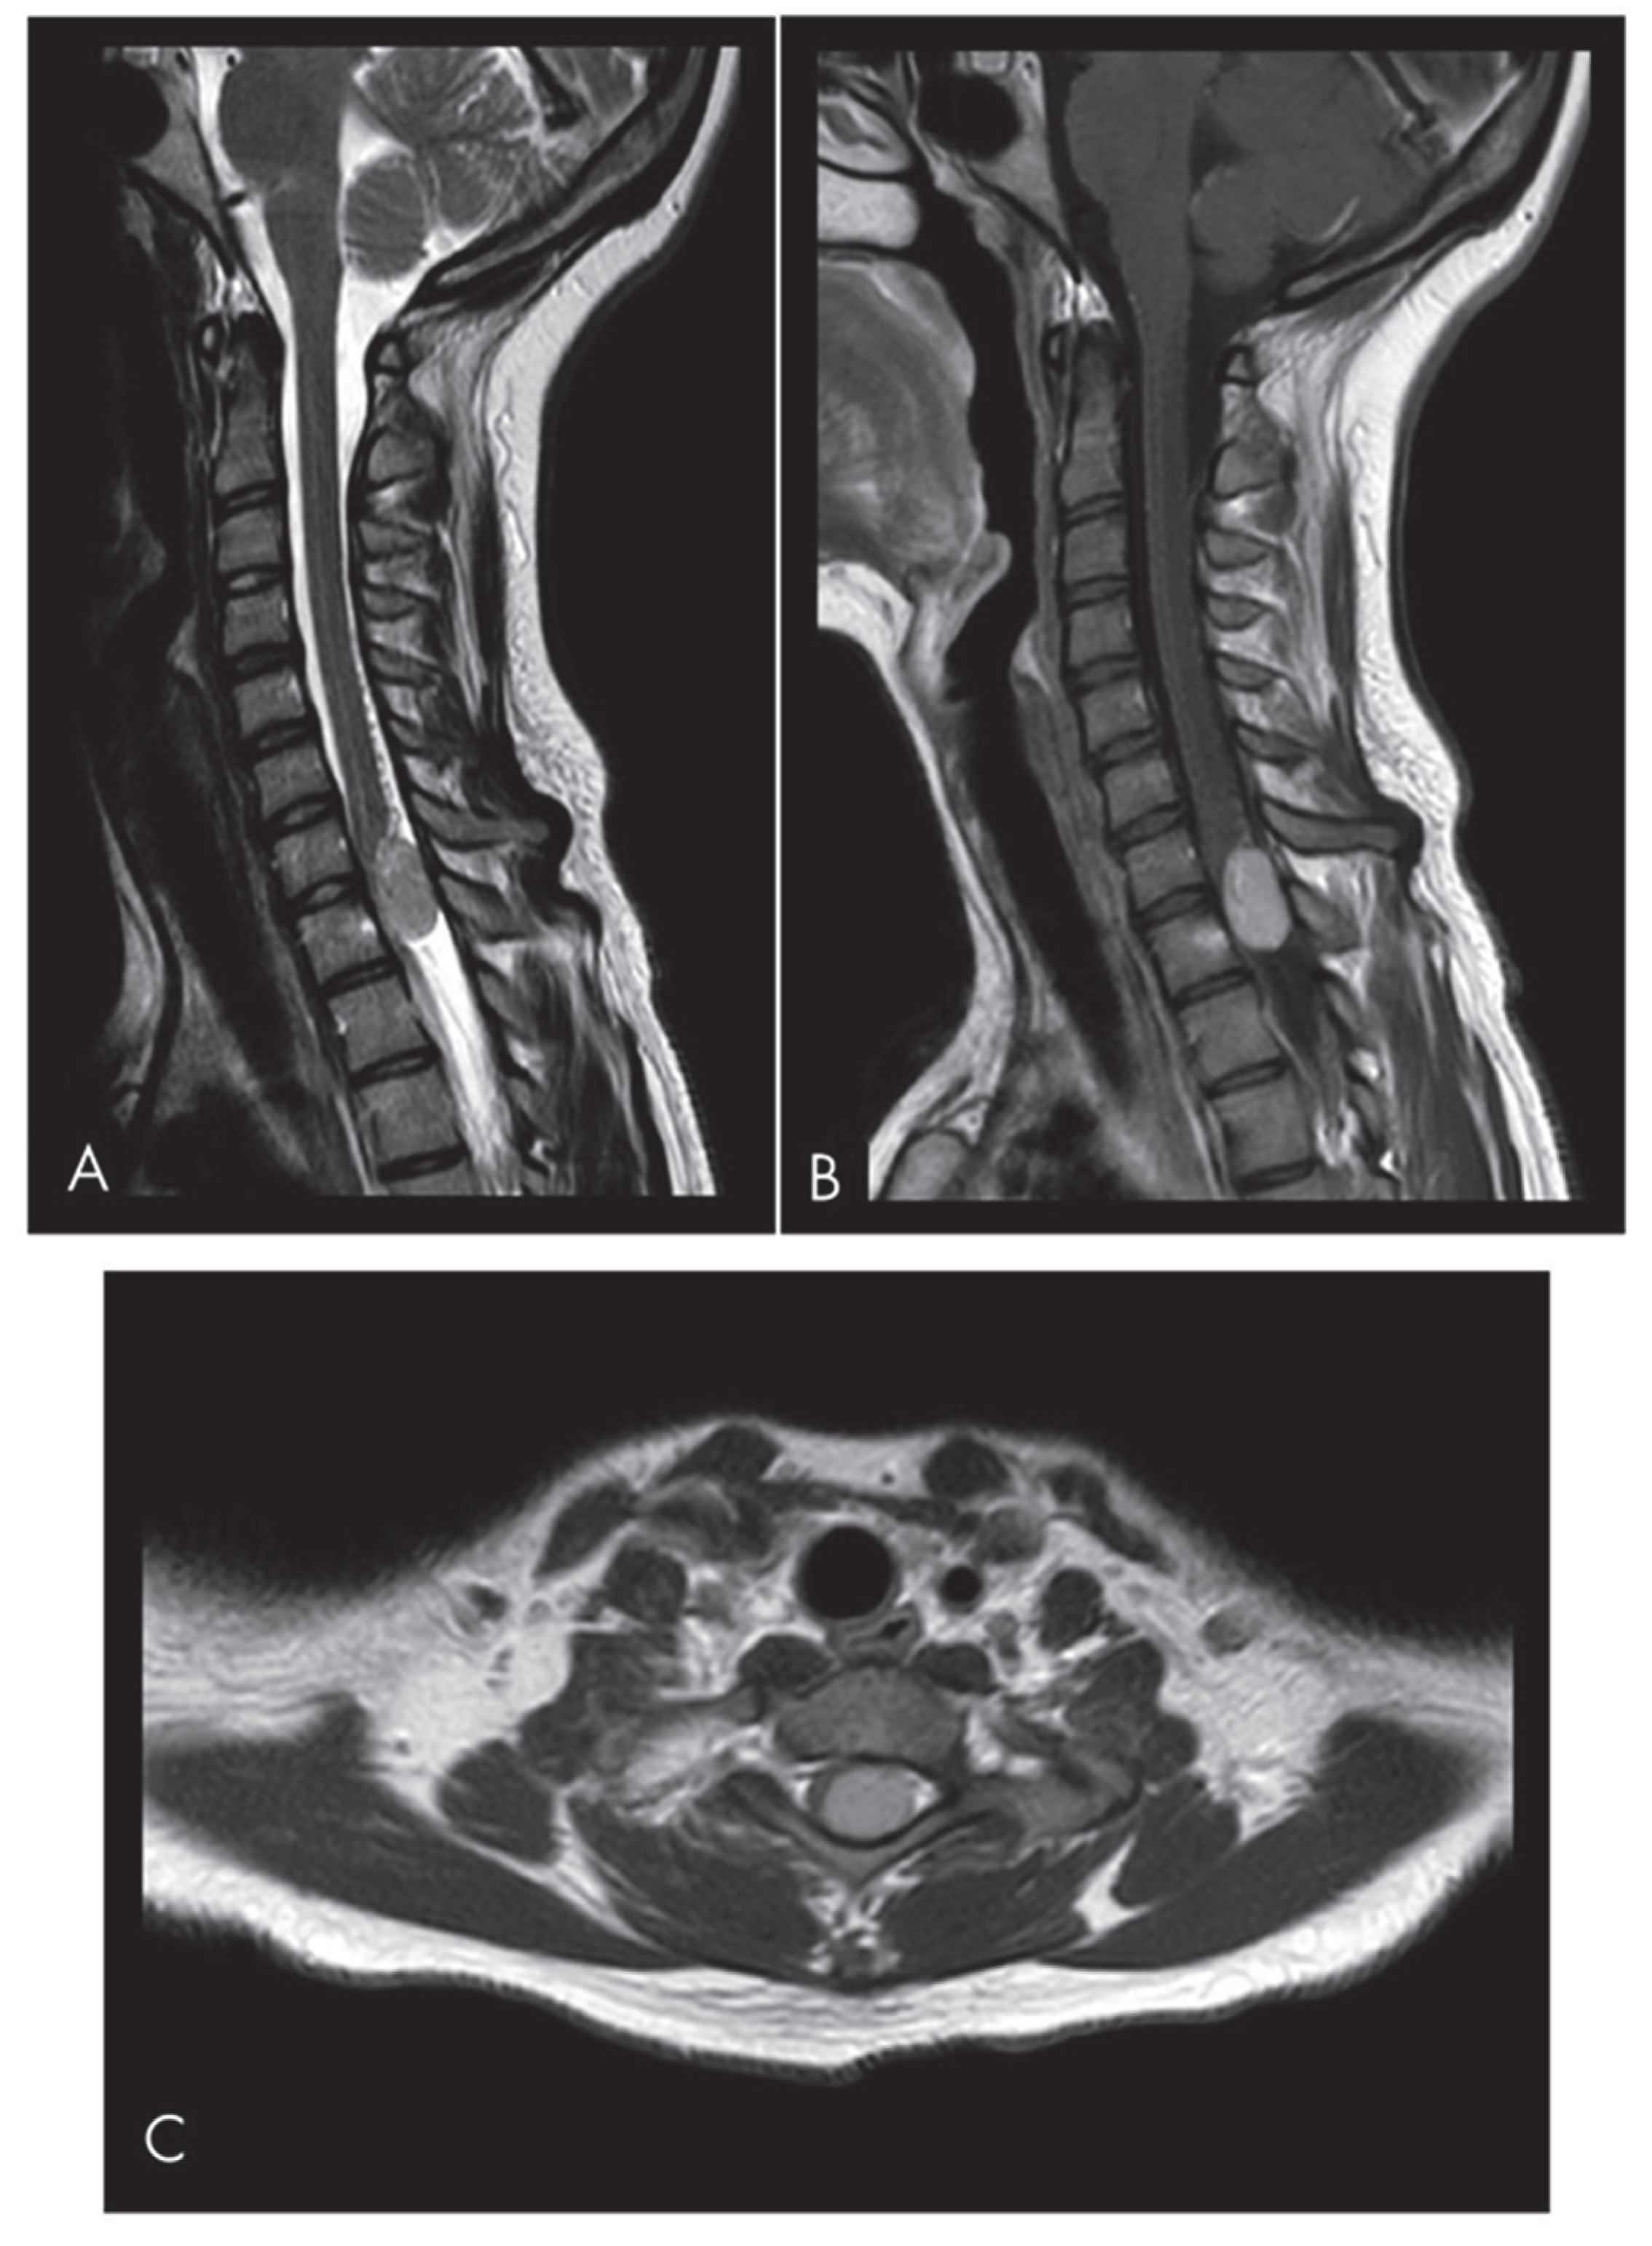

2. Case Presentation

| Present case | 1 | F | 15 | C7-T1 | Intradural Extramedullary | Lower limb hypoesthesia and weakness, mild urinary incontinence | GTR No RT | No | 16 |